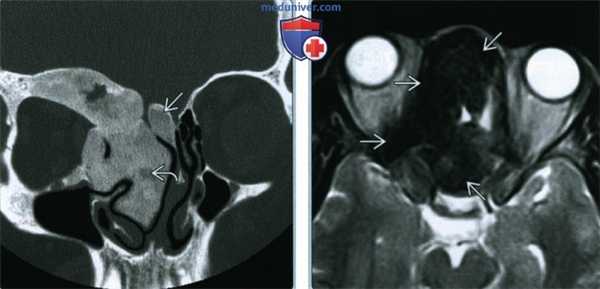

(Слева) При аксиальной «костной» КТ определяются классические признаки фиброзной дисплазии: выраженное вздутие левой верхнечелюстной пазухи с асимметричным выбуханием левой щеки, типичный вид «матового стекла». Обратите внимание на значительное уменьшение объема воздушной полости.

(Справа) При корональной костной КТ определяется фиброзная дисплазия с поражением правой нижней носовой раковины и латеральной стенки носа. Определяется выраженная экспансия раковины с изменениями в виде «матового стекла».

(Слева) При корональной «костной» КТ определяется экстенсивная фиброзная дисплазия орбит, петушиного гребня, решетчатой кости, среднего носового хода справа. Носовая перегородка отклонена влево.

(Справа) При аксиальной MPT Т2 в зоне фиброзной дисплазии определяется характерный выраженный гипоинтенсивный сигнал. Эти изменения типичны, когда наблюдаются совместно с «матовым стеклом» на КТ, и более диагностически значимы, чем гиперинтенсивные на Т2 очаги.